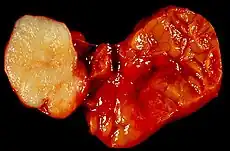

Parotid gland tumour | |

Salivary gland tumours, also known as mucous gland adenomas[1] or neoplasms, are tumours that form in the tissues of salivary glands. The salivary glands are classified as major or minor. The major salivary glands consist of the parotid, submandibular, and sublingual glands. The minor salivary glands consist of 800 to 1000 small mucus-secreting glands located throughout the lining of the oral cavity.[2] Patients with these types of tumours may be asymptomatic.[1]